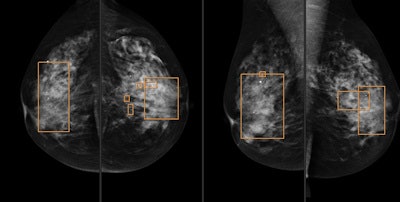

For the single reading, radiologists were selected based on their previous performance, according to the authors. They read the mammograms and made a decision whether to recall the patient, at which point the CAD marks were engaged. The radiologists then revised the marks and made a final decision.

If the final decision was that the mammographic findings were BI-RADS 1 or 2, CAD marks were not considered. If the finding was considered to be BI-RADS 0, 4, or 5, the patient was recalled and the radiologist wrote down the type of recall:

- Type A: The radiologist had found a mammographic finding that CAD did not mark.

- Type B: The radiologist had found a mammographic finding that CAD also marked.

- Type C: The radiologist found the mammogram to be BI-RADS 1 or 2 but after considering the CAD marks, determined a lesion could be present and decided to recall, meaning CAD changed the radiologist's mind.